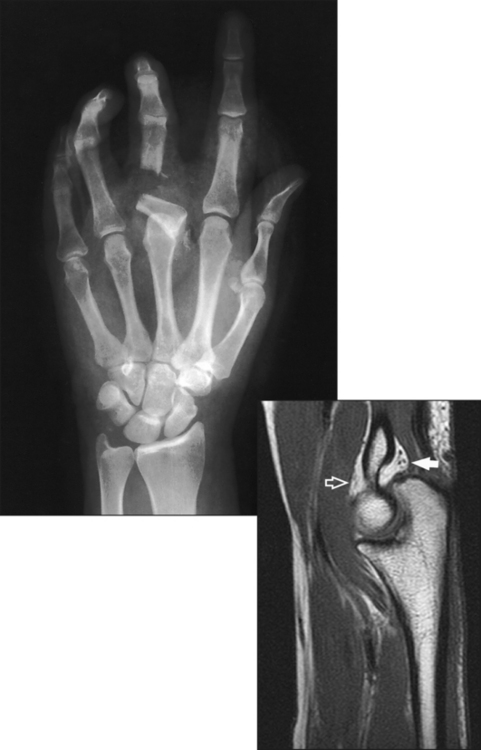

The anterior or palmar surface of the wrist is concave from side to side and forms the carpal sulcus (Figs. 4-2 and 4-3). The flexor retinaculum, a strong fibrous band, attaches medially to the pisiform and hook of hamate and laterally to the tubercles of the scaphoid and trapezium. The carpal tunnel is the passageway created between the carpal sulcus and flexor retinaculum. The median nerve and the flexor tendons pass through the carpal canal. Carpal tunnel syndrome results from compression of the median nerve inside the carpal tunnel.

Fig. 4-2 Axial MRI of wrist. Bones in same position as in Fig. 4-3. Note arched position of carpal bones and carpal sulcus protecting tendons of fingers (black circles within sulcus) and median nerve (white arrow). Flexor retinaculum (black arrow) is also seen.